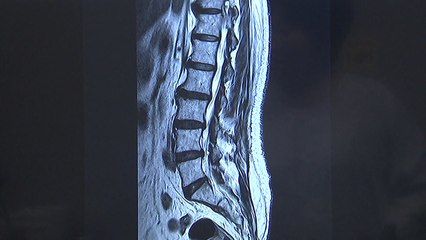

[앵커]br 요즘 같은 장마철에 무릎에 통증이 있는 사람은 더 견디기 힘듭니다.br br 무릎이 기압과 습도, 온도 변화에 민감하기 때문인데 무릎 주변을 따뜻하게 하고 가벼운 스트레칭 등으로 근육을 풀어주면 통증 완화에 효과를 볼 수 있습니다.br br 임상호 기자의 보도입니다.br br [기자]br 52살 이은숙 씨는 2년 전부터 무릎에 통증을 느꼈습니다.br br 아직 나이도 젊어 별다른 문제가 없을 것으로 생각하고 놔뒀는데 최근 통증이 심해지고 밤에 자다가 아파서 깨어나기도 해 병원을 찾았습니다.br br [이은숙 관절염 환자 : 큰 문제가 없더라도 가서 조기에 점검도 좀 받고 물리치료 받으면 편안해진다고 (주위에서) 가라고…. 저도 조기 점검을 좀 받아서 요새 좀 편안해지고 싶은 마음이 있더라고요.]br br 무릎관절염 환자는 꾸준히 늘어 지난 2011년 233만 명에서 2013년에는 247만 명, 지난해에는 260만 명으로 증가했습니다.br br 지난해 진료받은 환자를 봤더니 남성이 75만 명인데 여성은 185만 명으로 여성환자가 훨씬 더 많았습니다.br br 특히 요즘 같은 장마철에는 무릎 관절이 아픈 사람에게 고통이 더 큽니다.br br 대기의 압력이 낮아져 상대적으로 높아진 관절 내부 압력으로 관절에 통증이 생기고, 비가 와서 온도가 낮아지면 혈액 순환을 느리게 해 근육과 인대로 가는 영양분 등이 줄어 통증을 더 악화시킵니다.br br [송상호 정형외과 전문의 : 무릎 주변에 있는 압력 변화라든지 혈액 순환이 덜 돼서 무릎에 통증이 오는 경우가 많은데, 이럴 때는 무릎 주변을 따뜻하게 해서 혈액 순환을 좋게 해서 근육을 풀어주면 관절의 통증을 덜 하게 하고….]br br 운동량이 부족해도 관절의 기능이 떨어지므로 실내에서 가벼운 스트레칭 등으로 근육을 풀어주는 것도 도움이 됩니다.br br 하지만 무릎 통증이 이어질 경우 연골 등에 이상이 있을 수 있어 전문의의 진단과 치료를 받는 게 좋습니다.br br YTN 임상호입니다.br br ▶ 기사 원문 : ▶ 제보 안내 : , 모바일앱, 8585@ytn.co.